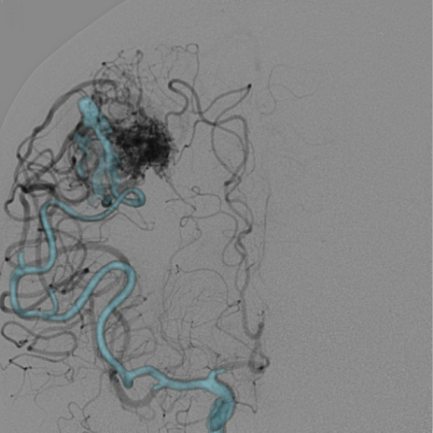

治疗方案及结果: 为了进一步详细观察畸形团形态和大小,需要行3D采集,仅需5秒即可完成血管的三维扫描。  GE提供快速血管提取功能,只需确认血管起点与终点,便可迅速找出供血血管路径,另外,通过使用三维智能路径图可以实时引导治疗过程,

病例点评及临床价值: 由于动静脉畸形团体积较大,且分支血管杂乱无章,因此很难一眼看出畸形团的供血动脉。GE提供快速血管提取功能,只需确认血管起点与终点,便可迅速找出供血血管路径,另外,通过使用三维智能路径图可以实时引导治疗过程,并且在此过程中不论机架、导管床如何变换角度和位置,只要患者相对导管床的位置不变,那么三维智能路径图会始终和患者实际情况完全精准对位,避免了二维路图时需要反复造影的不便。不仅可提高手术精度,还能减少造影剂的使用,节省介入操作时间。